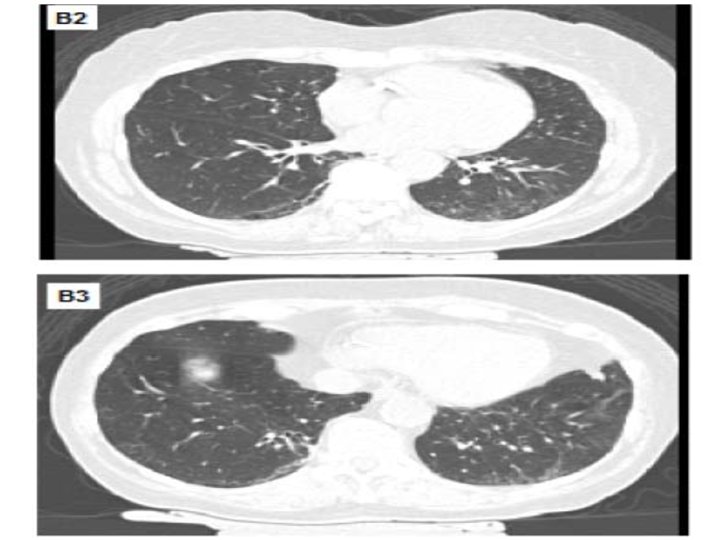

Interstitial Lung Abnormalities • Increased lung density on CT scans in patients with no history of ILD • 2‐ 10% of the population • Association with reduction in PFT, exercise capacity, development of ILD, and mortality • Refer to pulmonary